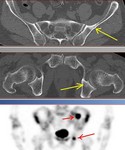

[画像診断]転移性骨腫瘍に対するFDG-PETと骨シンチグラフィについて 2010-08-05